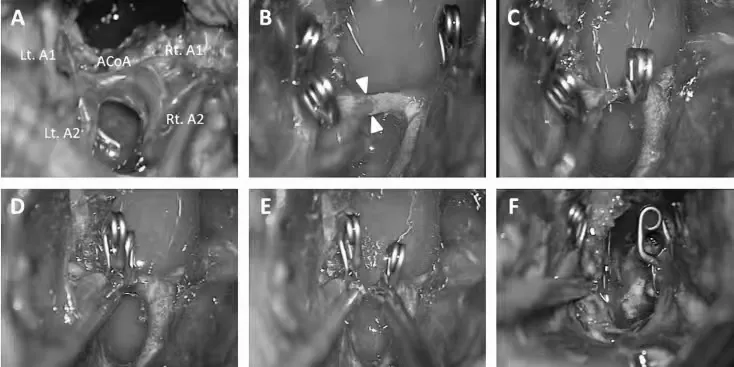

手术过程:

将累及视交叉的肿瘤切除,在垂体下方发现了垂体柄。

前交通动脉和椎板末端逐渐暴露。

打开椎板末端可以通畅进入到前三脑室并进行充分瘤内减压。

暴露后脑基底分叉和P1节段动脉,下丘脑和后循环血管完整保留。

前交通动脉意外地被拉伸撕裂,由于无法修复撕裂的前交通动脉,因此决定分离,从而在前交通动脉的两个A2段中维持供血,夹闭并分离前交通动脉。

控制好出血及保证血管通畅,可保证残留肿瘤的顺利切除。